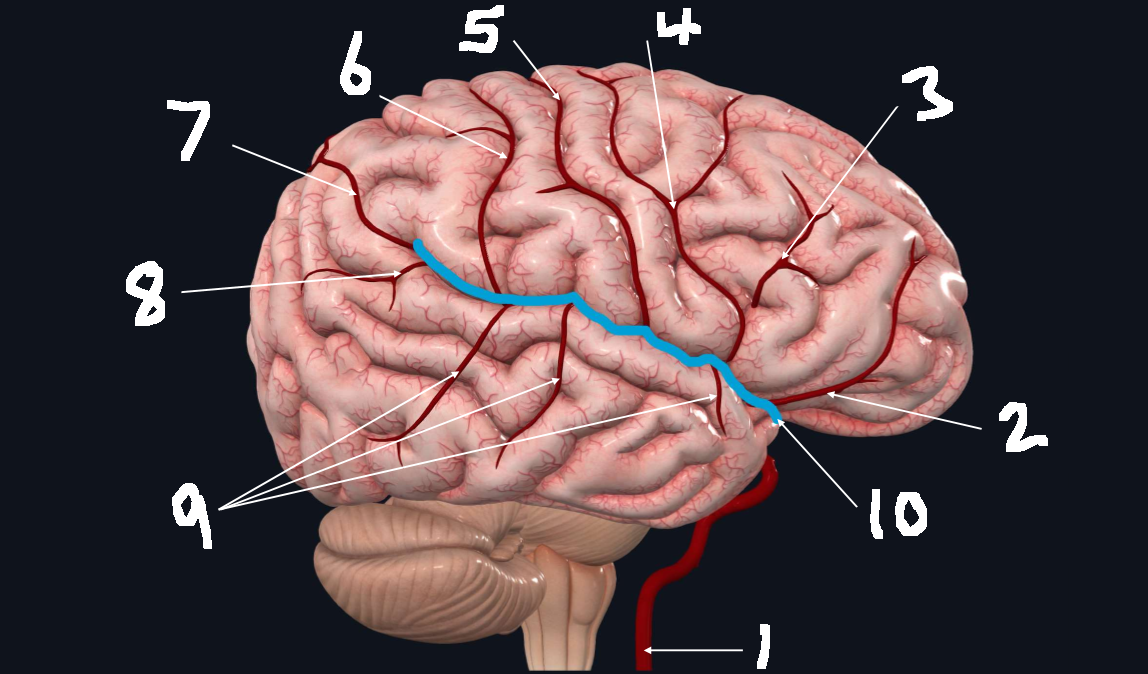

What is 1?

internal carotid artery

What is 2?

orbitofrontal artery

What is 3?

prefrontal artery

What is 4?

precentral artery

What is 5?

central artery

What is 6?

postcentral artery

What is 7?

posterior parietal artery

What is 8?

angular artery

What is 9?

temporal arteries (anterior, middle, posterior)

What is 10?

lateral cerebral fissure